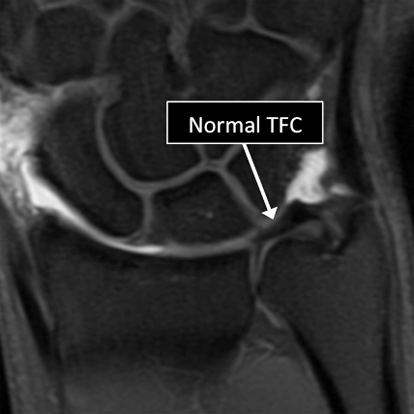

- Common things include fractures (broken bone), ligament and tendon tears, damage to the Triangular Fibrocartilage of the wrist (perforations and degeneration), osteoarthritis, tumors, among others.

Wrist MRI examinations showing normal (top) and abnormal (bottom) TFC.

Why Translational MRI of the wrist?

- In the wrist, as in many other parts of the body there are certain structures that can’t be seen (they look black or dark) with the standard MRI.

- There are new “software” programs that allow us to see structures with different contrast (bright versus dark).

- Some of these “invisible” or dark structures are unique to the wrist (Triangular Fibrocartilage or TFC) and others are found in other parts of the body (e.g. cartilage, tendons, ligaments, cortical bone).